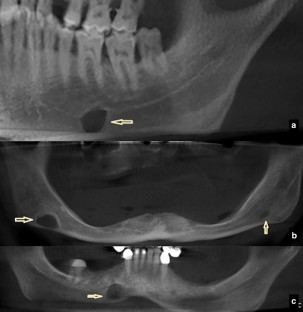

Fig. 2